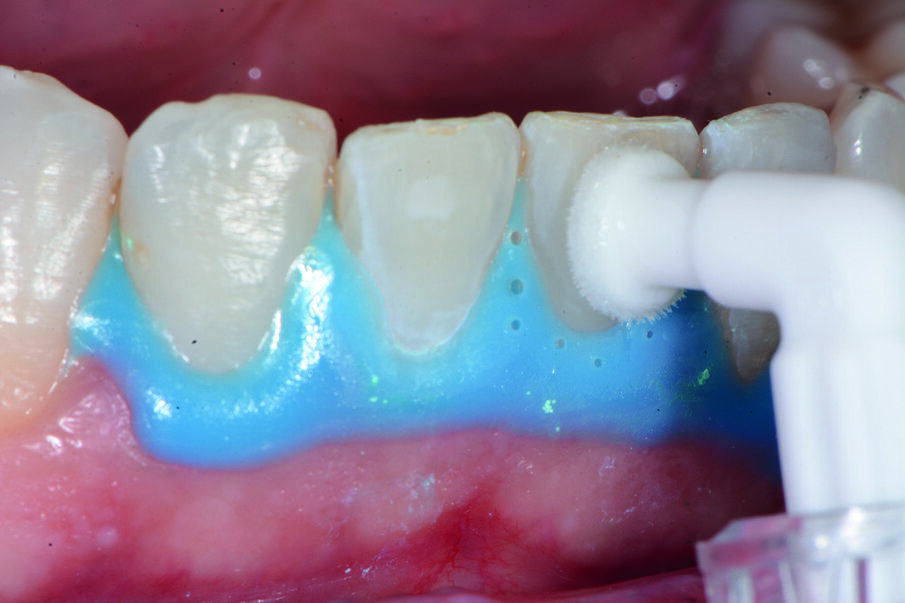

Prima del trattamento abbiamo applicato un rilevatore di placca alla fluoresceina Plac-o-Tect (Directa) per evidenziare la topografia della presenza di biofilm batterico nel cavo orale. Osserviamo la topografia del biofilm batterico presente e condividiamo con il paziente i siti più ritentivi di biofilm batterico in modo da avere una comunicazione non verbale del rivelatore, utile per il rinforzo motivazionale del paziente con l’obiettivo di migliorare l’efficacia dell’igiene orale domiciliare (Fig. 3).